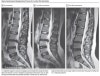

40대의 여성이 휠체어를 타고 척추 클리닉에 방문했습니다. 그녀는 2달동안 지속되는 다리 통증때문에 보행이 어려운 상태였습니다. 또한, 다리의 감각이 저하되고 근력이 떨어질 정도로 그녀의 상태는 위중해보였습니다.

허리 MRI 상으로도 요추 3-4번 사이에 크기가 큰 허리 디스크(요추 추간판 탈출증) 소견이 있어 허리 신경이 압박되고 있었습니다. 그녀는 다리 통증으로 걸을 수 없는 상태였기 때문에 수술을 권유받았지만 수술과 합병증에 대한 두려움 때문에 그녀는 보존적 치료를 선택했습니다.

한 달 뒤 그녀는 다리 통증이 상당히 감소되었으며 다시 허리 MRI 검사를 시행한 결과 디스크가 부분적으로 흡수되었음을 알 수 있었습니다.

환자의 첫 내원 후 8개월이 지난 뒤에는 전혀 증상이 없었으며 이학적 검사에서도 문제를 찾을 수 없었습니다. 다시금 MRI를 시행한 결과 탈출되었던 디스크는 더이상 보이지 않았습니다.

요추 3-4번 사이에 튀어나왔던 디스크가 시간이 지남에 따라 점점 흡수되는 것을 명확히 관찰할 수 있습니다. 허리 디스크 때문에 생겼던 통증, 감각저하, 근력저하 역시 시간에 지나면서 점점 좋아지는 것을 알 수 있습니다.

이처럼 튀어나온 디스크의 크기가 큰 경우도 비교적 짧은 기간(8개월)안에 완전히 흡수될 수 있음을 알 수 있었습니다.